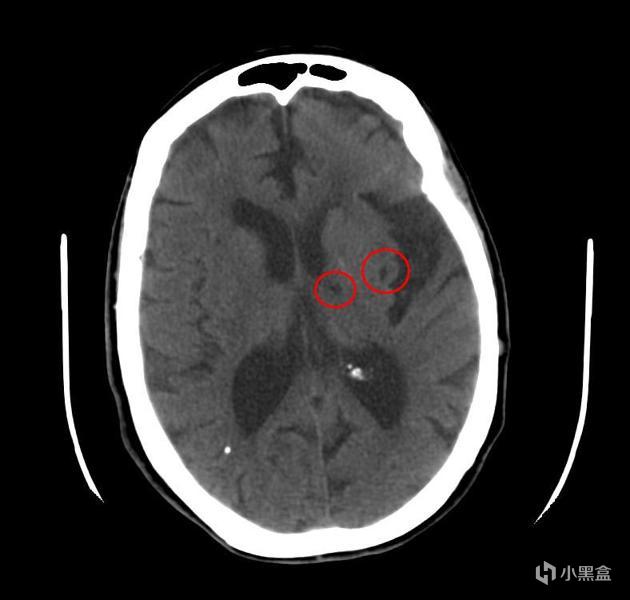

1、PFO相關卒中:近年來幾項大型的RCT結果表明,PFO導致的反常栓塞是造成心源性卒中的重要原因,大約佔到缺血性卒中的5%。

卒中就是我們常說的中風,或者說腦梗。一般血栓是在流速慢的靜脈系統形成,如果有卵圓孔這樣溝通動靜脈系統的通道,靜脈血栓就會進入動脈直達腦血管裏形成堵塞,所以PFO患者經常在片子上能看到梗死竈。

![]()